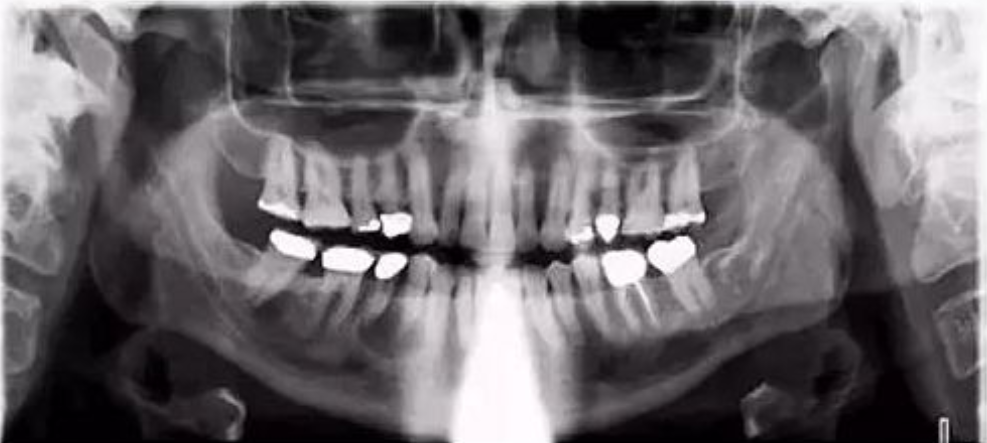

九、两侧下颌支与牙齿大小不同

【失误原因】

患者扭动。

【解决方法】

确保患者在全景成像时候处于直立稳定状态。